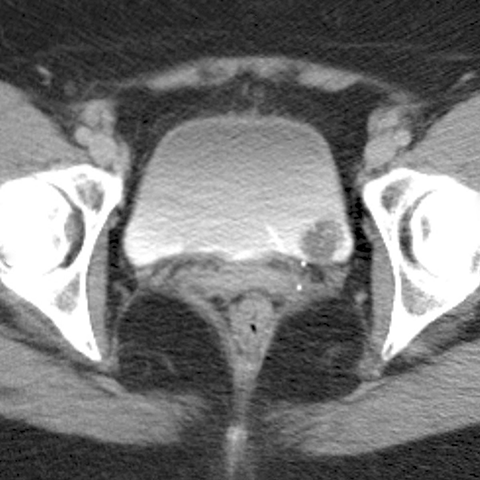

Bladder Cancer, contast-enhanced CT [2 of 2]